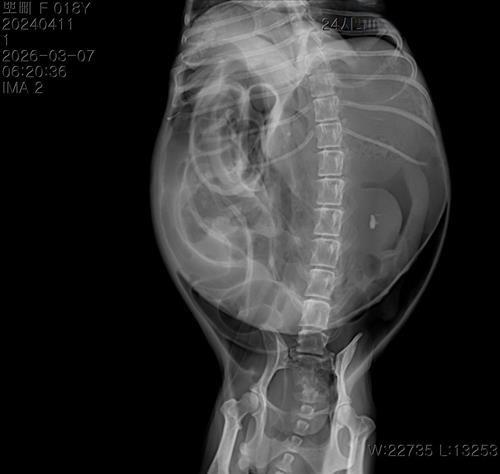

17살 말티즈 1.6 kg 였습니다. 엑스레이 하나는 복부팽창 찍은 이떄 혼수상태 일겁니다 또 다른 하나 사진은 이미 혼수상태 쇼크상태에서 천자 한 후 찍은 엑스레이 사진입니다

엑스레이 자세는 배가위로 가는 촬영 인거 같습니다. 뽀삐는 평상시에 배를 보이면 굉장히 싫어했었습니다

의사말 1번쨰 엑스레이 찍었을때 장기파열 두번쨰 뽀삐가 쇼크가 오고 혼수상태 일때 천자후 두번쨰 엑스레이 찍을때는 큰 덩어리로 보이는 종양 이라고 하였습니다